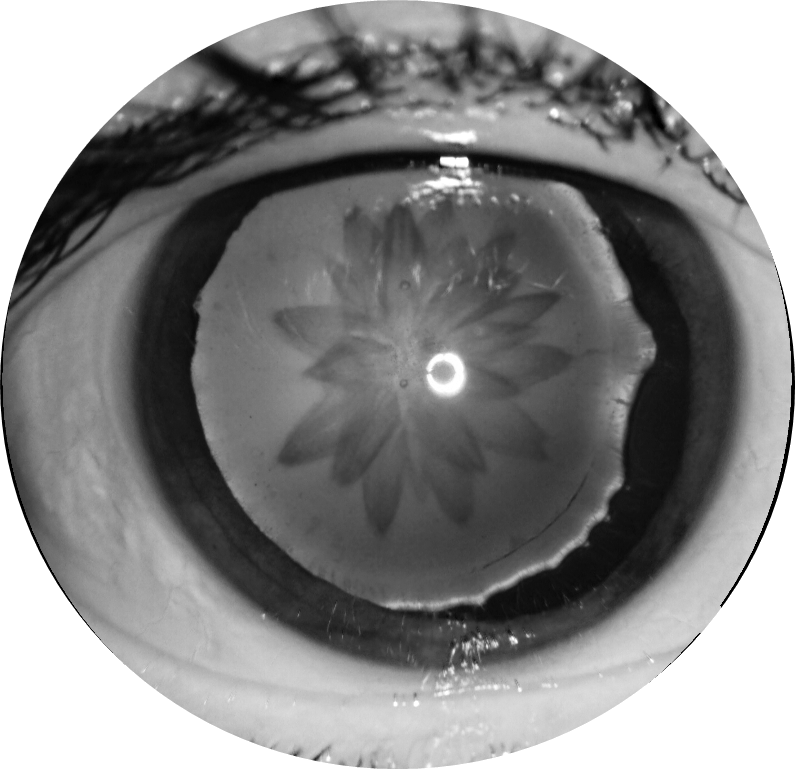

20 gün önce travmaya maruz kalan, görme keskinliğinde 2 mps düzeyine kadar azalma olan 56 yaşındaki kadın hastanın dilatasyonsuz sağ göz ön segment fotoğraflarını görmektesiniz. Tanı ve bulgularınız nelerdir? Lütfen cevabınızı aşağıya yazınız.

Bu ay size sağ gözünde 20 gün önce travmaya maruz kalma ve görme keskinliğinde 2 mps düzeyine kadar azalma olan 56 yaşındaki kadın hastanın dilatasyonsuz sağ göz ön segment fotoğrafları eşliğinde tanısını ve bulgularını sormuştuk.

Tanı: Travmatik katarakt, travmatik midriyazis, zonül defekti ve lens subluksasyonu’dur.